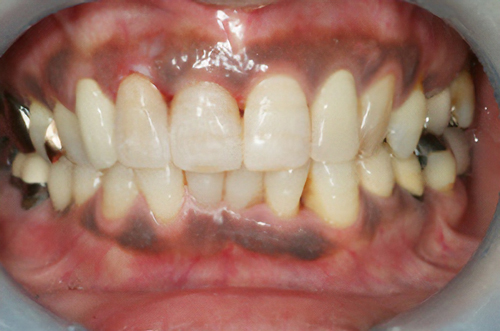

黒ずんだ歯肉の色をお薬で、キレイなピンク色の歯肉にします。

塗り薬の麻酔と薬液だけで10分程度、2回の治療でキレイなピンク色に。-

術前

術後